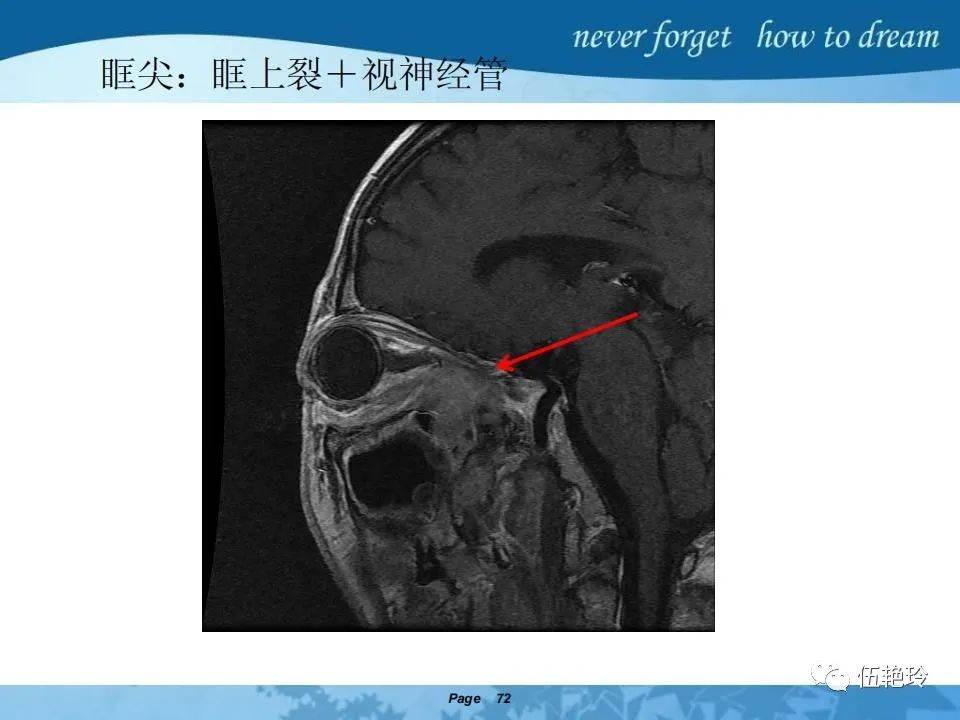

2.2 鼻咽特有的解剖途径:鼻咽癌原发灶循序进展的总途径:鼻腔(47.8%)→翼腭窝(15.2%)→ 眶下裂(3.2%)→眶尖(1.2%)→海绵窦(0.6%)。

2.31 向上颅内:①鼻咽顶壁→破裂孔(岩尖、斜坡)→蝶窦、海绵窦;②鼻咽顶壁→蝶骨基底部→蝶窦、海绵窦;③鼻咽侧壁→茎突前间隙→蝶骨大翼(卵圆孔)→海绵窦;④鼻咽侧壁→茎突前间隙→翼腭窝→ 颞下窝;⑤鼻咽前壁→鼻腔→翼突、翼腭窝→眶下裂→眶尖→海绵窦;⑥鼻咽前壁→鼻腔→上颌窦、筛窦;